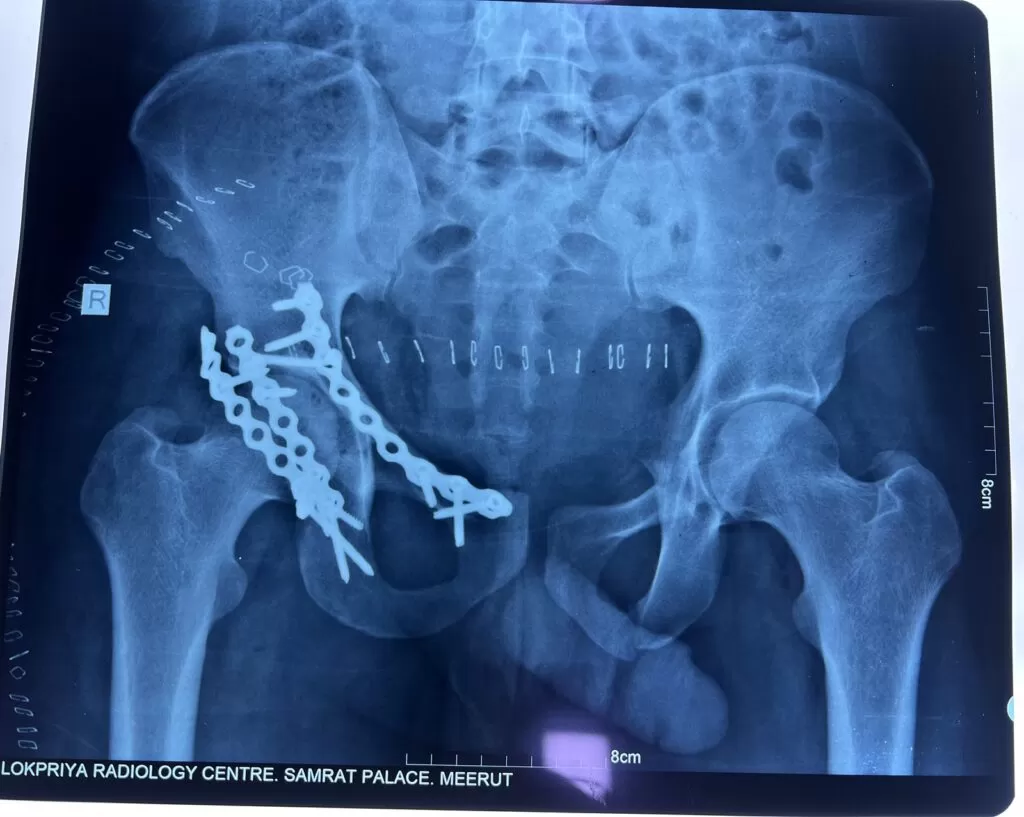

Mr. Amjad

Name: Mr. Amjad

Date of Operation: 12 Apr 2024

Age: 28 Years